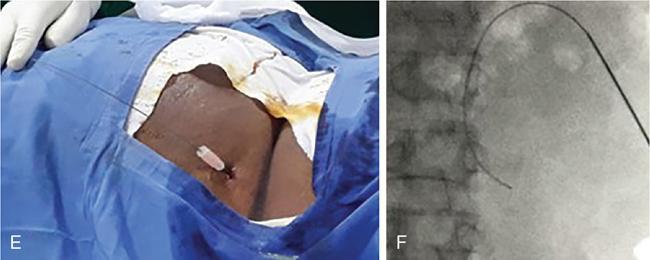

NONVASCULAR RENAL INTERVENTION Amitha Vikrama Nonvascular renal interventions have come a long way and have significantly reduced the surgical mortality and morbidity. It also paves way for short hospital stay and thus reducing the chances of nosocomial infection. They are usually pinhole or keyhole procedures with less distortion of the anatomy and physiology. They vary from image-guided aspiration/biopsy to percutaneous nephrostomy to complex procedures like ureteric stenting, strictureplasty, percutaneous nephrolithotomy etc. Iversen and Brun were the first to perform percutaneous renal biopsy of native kidneys in 1951. Over the years, newer imaging and biopsy techniques have evolved which have increased the biopsy yield to >95% and significantly reduced the complications of renal biopsy, resulting in decreased mortality rates from 0.12% to 0.02% during the last 50 years NOTE: Solitary renal mass lesions suspicious for malignancy should not be subjected to percutaneous biopsy, as there are chances of tumour seeding along the biopsy track. Excision biopsy is preferred for those lesions as it can be curative. USG-guided renal biopsy is the preferred method over blind biopsies. It avoids nontarget biopsies and reduces bleeding risks. Usually the lower pole of the kidneys is preferred site in native renal biopsy. The needle has to be directed into the lower cortex and care taken to avoid renal medulla and collecting system. 18G trucut biopsy needles are usually used in adults. In paediatric population, 20G can be used. Rarely, Coaxial technique is used in very obese patients and in those who are unable to lie prone. It is usually done as an inpatient procedure. Four hours of fasting is required to prevent aspiration of gastric contents during the procedure. Antiplatelets and anticoagulants are stopped at least 3–5 days prior. Informed written consent has to be taken after explaining the risks and benefits of the procedure. Patient is to be positioned in prone and USG-guided marking of the site of biopsy done prior to cleaning and draping. The depth of the renal cortex from the skin surface has to be noted. If the ribs are coming in line with the lower pole cortex, then a cranially angulated path is preferred. After infiltration of 2% lignocaine, the biopsy needle is advanced up to and not into the lower pole cortex. As the kidney keeps moving with respiration, the biopsy should be properly timed to avoid hitting the collecting system and medulla. This method is real-time ultrasound guided renal biopsy (Fig. 10.21.1.1). There is another method practiced in few of the institutes where the location of lower pole of the kidney is marked on the skin after ultrasound screening. The marking corresponds to the lower most renal cortex at the end of normal inspiration and the biopsy path will be perpendicular to the bed without any craniocaudal or mediolateral angulation. The distance between the skin and the renal cortex is measured. The patient will be instructed strictly not to change his position. Then the biopsy will be done blindly without any real time USG guidance. With this method, more number of patients can be biopsied in a short interval time. In a transplanted kidney, which is usually grafted in the iliac fossa, biopsy can be obtained from upper or lower pole. Points to remember: Cortical tangential and cortical non tangential approaches have been described (Fig. 10.21.1.2). Cortical tangential approach is described to have better diagnostic yield with lesser complications. In this approach, the needle track will be almost parallel to the capsule so that only the cortical tissue is targeted (Fig. 10.21.1.3A–C). Renal biopsy can also be done with coaxial technique. In this method, a coaxial needle, one size bigger than the biopsy needle, usually 17G, is inserted up to the renal capsule. The stylet is then removed and the 18G biopsy needle is inserted through the coaxial needle and the required number of biopsy specimens obtained. After this, the rent in the capsule can be sealed off with gelatine plugs before removing the coaxial needle. This helps in preventing bleeding complications. In patients with high risk of bleeding due to coagulation abnormalities, transjugular renal biopsy can be done in which renal vein is cannulated and biopsy done from within (Fig. 10.21.1.3D–F). In obese patients who cannot lie prone, biopsies are done in lateral or oblique lateral positions under CT or USG guidance. CT guidance is especially helpful when the visualization of the kidney is difficult on ultrasound. In these cases, coaxial technique is always helpful. In 2019, KHA-CARI guidelines were first published for renal biopsy. A few of the salient recommendations are given below: It is an image-guided procedure in which the renal pelvicalyceal system is accessed percutaneously which is predominantly used for decompressing an obstructed system and also for various other therapeutic procedures. It is usually done under local anaesthesia and IV sedation. Major procedures might require general anaesthesia. All routine preprocedural blood tests and coagulation profile should be done. Appropriate antibiotics are administered intravenously prior to the procedure. 21G needle, 018 and 035 wires, appropriate dilators, sheath and pigtail drainage catheter. Ultrasound and fluoroscopy is required for guidance. Patient is usually positioned prone on the table. Under special circumstances, lateral or oblique positions are also used. After instillation of local anaesthesia, a 21G needle is used to access the renal calyx under USG guidance. Once the urine flow is seen, nonionic contrast is injected to delineate the renal collecting system. A 018 wire is passed through the needle into the pelvicalyceal system and later exchanged for a 035 wire. Appropriate tissue dilators are used to dilate the track before placing a pigtail drainage catheter. The drain is secured by stay sutures and connected to a urobag. The initial urine sample is to be sent for culture and sensitivity (Figs. 10.21.1.4–10.21.1.6). Ureteric stenting was first described by Zimskind et al endotracheal tube al in 1967. It is one of the commonest procedure done in urology practice It is usually done after doing a percutaneous nephrostomy. The percutaneous nephrostomy (PCN) drain is replaced with a 6F or 8F sheath over a guidewire and ureterogram is obtained to assess the site of stricture or obstruction. Using a catheter and guide wire combination, the stricture is negotiated and the exchange length hydrophilic wire is parked in the bladder. The ureteric length is measured and appropriate-sized double J (DJ) stent is inserted over the wire. Care is taken to get the loops formed at both ends of the DJ stent so that stent migration is prevented (Fig. 10.21.1.7). A variety of delivery systems are available for the deployment of the ureteric stent exist: pusher mechanism, string release and sheath (similar to an inferior vena cava (IVC) filter). Post stent insertion, the nephrostomy drain can be retained for a couple of days. The drain is closed externally and USG screening is done the next day to confirm antegrade flow after which the drain can be removed.